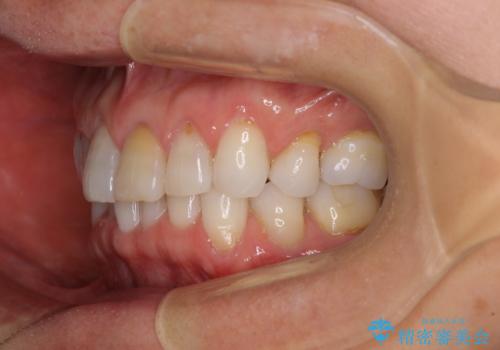

矯正治療の後戻り インビザライン・ライトでの再矯正

- 上下前歯を中心に、以前行った矯正治療の後戻りが気になるとのことで来院された患者様です。

後戻りは軽度であったため、インビザライン・ライトにて治療を行うこととしました。

矯正治療後は、再度後戻りすることを極力回避するために、下顎前歯の舌側を細いワイヤーを用いて保定することとしました。